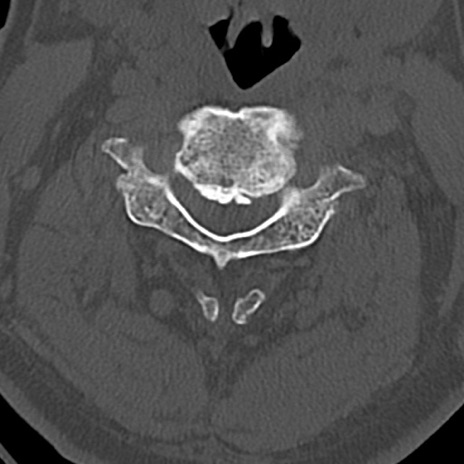

頚椎CT

横断像